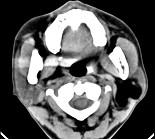

问题 男性38岁,左侧腮腺渐进性肿大1年,无压痛,CT扫描如图所示,请选择正确的描述和结论()

选项 A.左侧腮腺区见低密度肿块,CT值约为-200HU B.肿块边缘清楚,未见邻近结构受侵 C.考虑为囊肿 D.考虑为脂肪瘤 E.考虑为血管瘤

答案 ABD